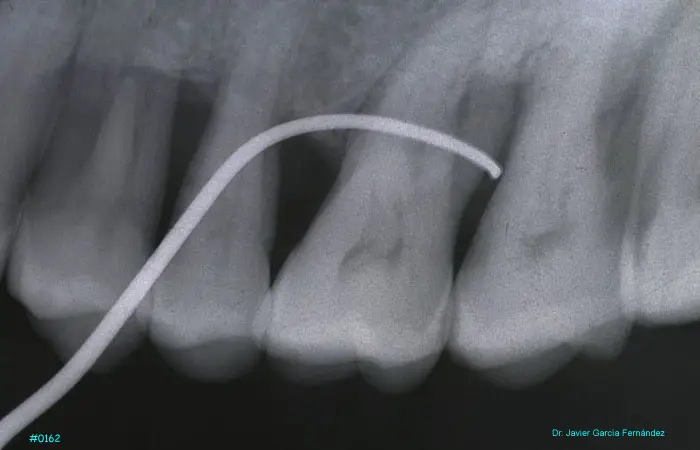

Atlas of Surgical Techniques in Periodontics. Chapter II. Atlas de Técnicas Quirúrgicas en Periodoncia